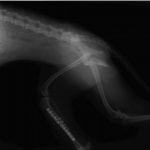

症例:交通事故による椎体脱臼

柴犬:9歳、避妊雌

交通事故直後、胸腰部に激しい疼痛、両後肢に完全麻痺を認め、シェフシェリントン徴候を呈していました。レントゲン検査において、第11-12胸椎間の脱臼が認められました。

脊髄の減圧、脊柱管の再構築・安定化を目的に、片側椎弓切除術およびMatrixMANDIBLE Plateによる椎体固定を実施しました。

隣接椎体を架橋するようにプレートを設置しました。

術後レントゲン写真